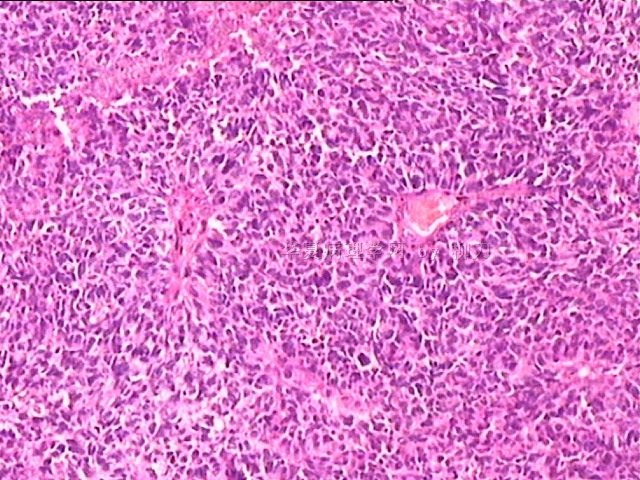

女,34y,头痛一月,右额叶占位:5*5*4cm。囊性区域,4cm。大体:3.5x3x1cm灰白间暗褐色组织一堆,质嫩。临床诊断1:胶质瘤,2:血管母细胞瘤。

本人县级医院头颅手术少,考虑胶质母细胞瘤。大家指导指导。

同意胶质母细胞瘤。细胞异型、坏死、核分裂、血管内皮肿胀增生均可见到。

This is certainly a WHO grade IV malignant neoplasm. While most likely a glioblastoma, I would carefully rule out PNET by staining for GFAP and neuronal markers such as synaptophysin, NeuN and NSE. Rarely, PNET may shows marked pleomorphism and indistinguishable from glioblastoma on HE stain.

同意马老师的意见,该肿瘤从形态及年龄来看考虑PNET或GBM,须标记Syn、NSE、S-100、NeuN和GFAP来鉴别。

结合图片细胞形态特点考虑胶质母细胞瘤,组化标记排除其他